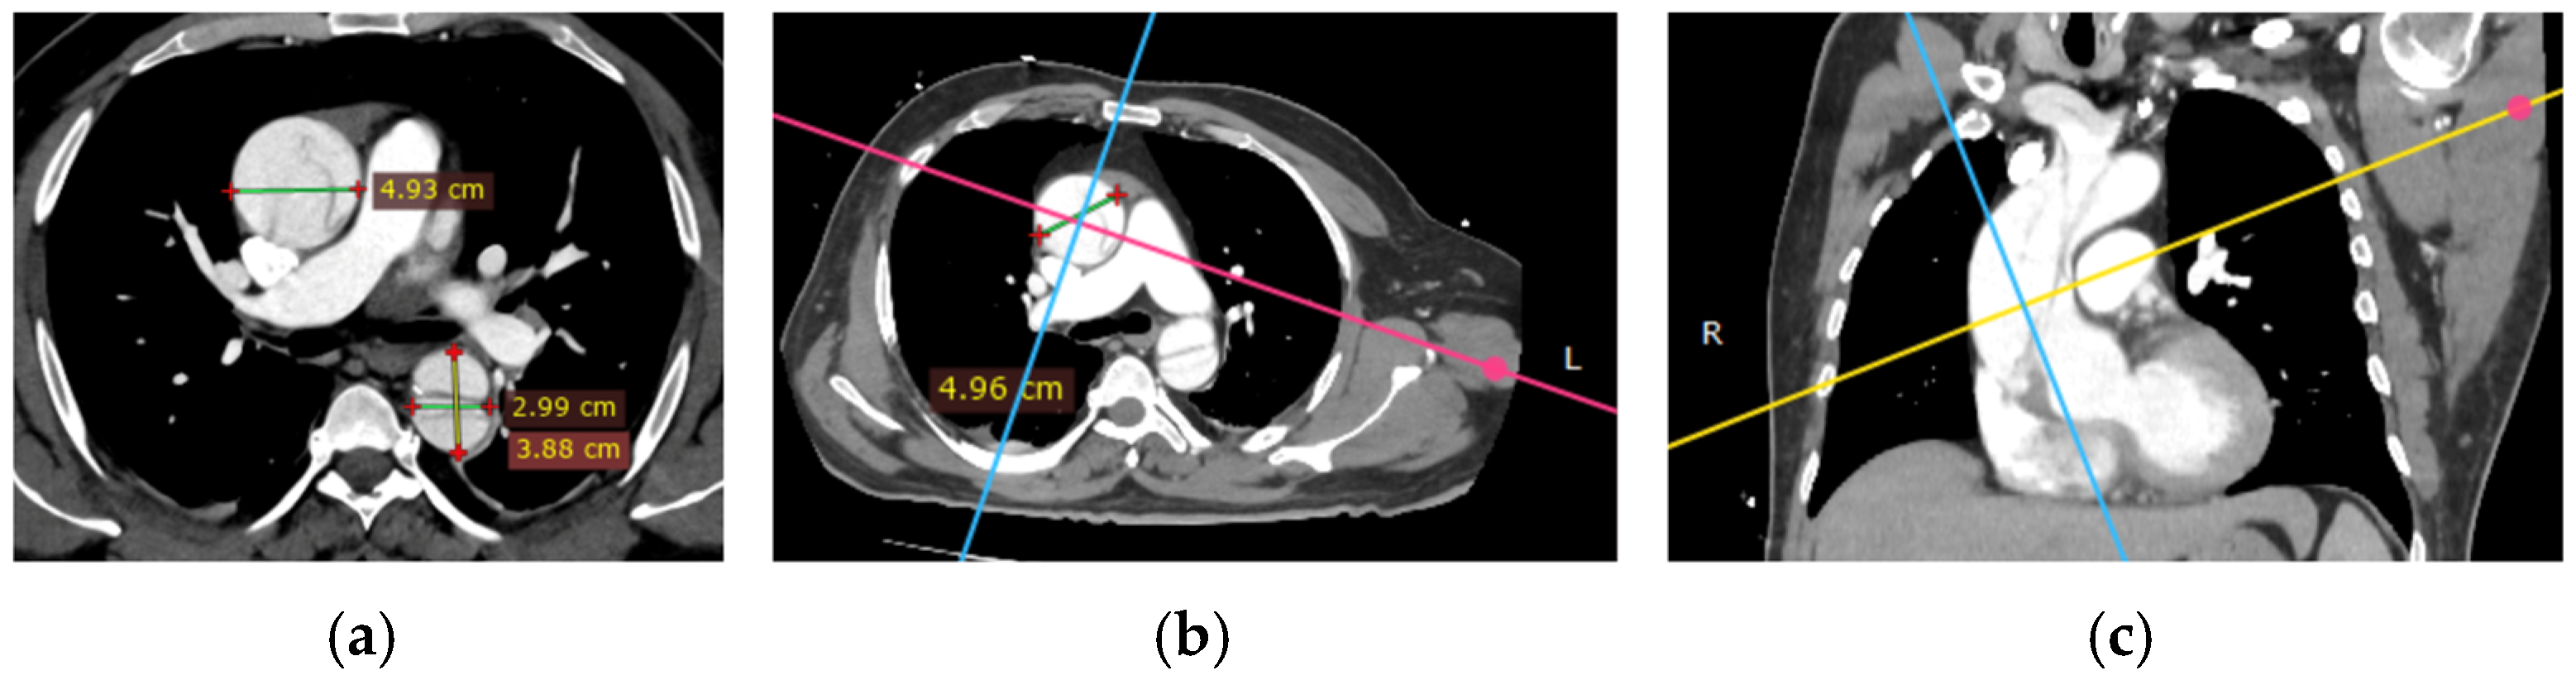

Imaging is essential for the diagnostic confirmation of aortic dissection. All patients received thoracic CTA and TTE. In the radiological evaluation of patients with aortic pathologies, precise measurements of the aortic lumen play a crucial role in assessing disease severity and planning interventions. Using true perpendicular sections, accurate diameters of the ascending and descending aorta were obtained. The following images (Figure 4) demonstrate this approach and provide representative measurements for reference.

Figure 4. Radiological measurements of the aortic lumen using perpendicular sections in a patient with aortic pathology: (a) axial view showing key diameters at different levels: ascending aorta (4.93 cm), descending aorta (2.99 cm), and distal descending aorta (3.88 cm; (b) the cross-sectional plane used for accurate measurements (4.96 cm); (c) coronal reconstruction illustrating the orientation of the imaging planes relative to the aortic arch and descending aorta, ensuring perpendicular alignment for precise dimensional assessment. These measurements are critical for diagnosing and monitoring the progression of aortic diseases and planning surgical or interventional management.